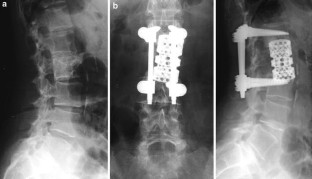

Introduction: The objectives of surgical interventions for tumoral lesions of the spine include the establishment and improvement of tumor-related symptoms. Anterior tumor resection followed by reconstruction indicated if surgical treatment allowed a marginal removal of the tumor or could extend the individual survival rate in combination with adjuvant therapy options. Sufficient re-stabilization depends on adequate anterior column reconstruction. The purpose of this retrospective study was to present our experiences and results after anterior tumor resection followed by reconstruction with the expandable vertebral body replacement device (VBR, Ulrich, Germany) based on clinical application over 4°years. Patients and methods: We carried out an anterior tumor resection followed by reconstruction using an anterior extendable device in 32 patients with different spine tumors between 1996 and 2000. A retrospective evaluation was executed considering the patients medical records and radiological findings. Additionally, a clinical and radiological investigation of still living postoperative patients was carried out. Results: The mean surgical time of all evaluated patients was 317.2 min. The average blood loss was 1,272.5 ml. According to the Tokuhashi score, patients with a postoperative survival time of at least 12 months demonstrated a score value ≥9 points. According to our evaluated patients group metastatic lesions of the spine represented the largest group (78.1%). The average survival rate of this group amounted to 18.4 months postoperatively. Considering primary tumors the average survival rate at the time of last re-examination amounted to 34.8 months postoperatively. Preoperative neurological pathologies were present in 12 patients (Frankel stage C--D). During the postoperative monitoring period 58.3% of the patients demonstrated an improvement in initial neurological findings. There were no intraoperative complications or perioperative deaths. Implant dislocations were not observed. Conclusion: On account of the underlying, the anterior tumor resection with supplementary instrumentation represented a sufficient procedure in spinal tumor surgery. Adjuvant therapy can influence the postoperative survival period positively in addition to the surgical procedure. Following anterior tumor resection, extendable vertebral body replacements like the VBR device provide immediate spine stability by excellent defect adaptation. With regard to their intraoperative flexibility, expandable cages are more advantageous in contrast to non-expandable implants or bone grafts.